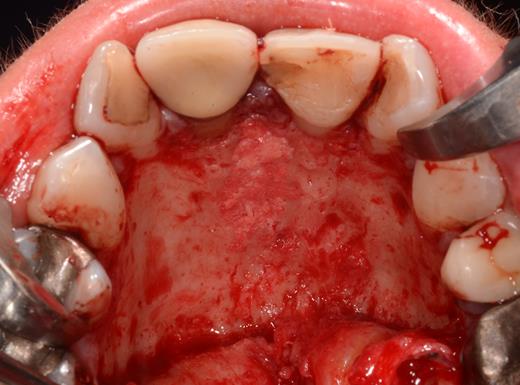

After a sulcular incision on the palatal side from teeth 15 to 25 and an incision in the midline of the palate omitting the incisive papilla and the two orifices of the NPD, two full-thickness mucoperiosteal flaps were raised. Thereafter, the incisive papilla and the whole contents of the incisive canal were enucleated (Figs 4–6). The bony incisive canal was filled with autologous bone harvested from the palatal region (bone scraper) (Fig. 7). A tension-free primary wound closure was achieved by moving the palatal flaps to the midline using single button and interdental vertical mattress sutures (Monocryl 4-0, Ethicon, Johnson & Johnson, USA) (Fig. 8). To avoid wound dehiscence and hematoma, an iodoforme gauze and a palatal plate were applied (Fig. 9). The patient was instructed to rinse three times a day with 0.1% chlorhexidine (formula hospitalis) for 2 weeks postoperatively. Sutures were removed after 14 days.

Excised soft tissue contents of the incisive canal including the neurovascular bundle and the incisive papilla.